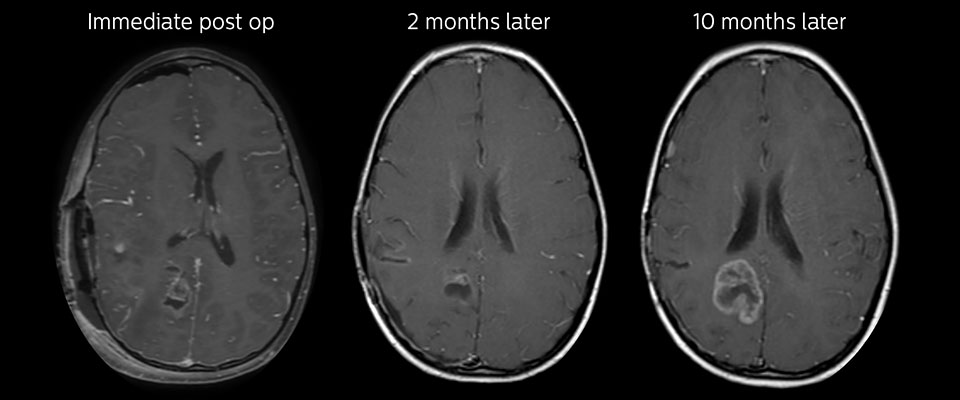

MRT mit APT nach der Resektion

Unmittelbar nach der Resektion wurde erneut eine MRT durchgeführt. Die T2-gewichteten und kontrastverstärkten T1-gewichteten Bilder lassen keine eindeutige Unterscheidung von Residualtumorgewebe und postoperativen Gewebeveränderungen zu. Auf dem APT-Bild ist noch ein hohes Signal zu sehen, das auf Residualtumorgewebe hindeuten würde.

Nachuntersuchung im Laufe der Zeit

In späteren Nachuntersuchungsscans weisen die kontrastverstärkten T1-gewichteten Bilder auf rezidivierendes Tumorwachstum hin. Daher wäre es interessant, den prädiktiven Wert von APT in einer großen Patientengruppe zu untersuchen.